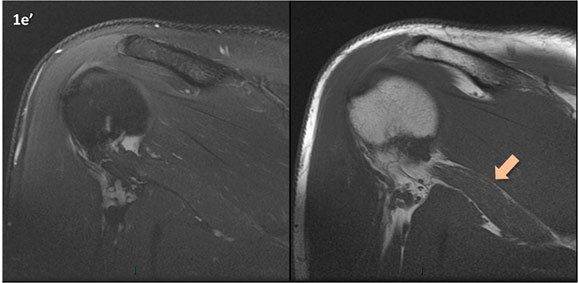

Figura 1 (a-g): Imagens consecutivas de RM no plano coronal nas ponderações DP com supressão de gordura (DP SG) à esquerda e T1 à direita. Clique na seta para passar as imagens.

Figura 1 (a-g)': Imagens consecutivas de RM no plano coronal nas ponderações DP com supressão de gordura (DP SG) à esquerda e T1 à direita mostrando . Clique na seta para passar as imagens.

Figuras 1b’ a 1g’ mostrando atrofia da porção superior do músculo redondo menor (seta salmão), com lipossubstituição mais evidente das mais fibras laterais (seta amarela). As fibras mais inferiores e mediais têm atrofia menos evidente.

Repare que estas alterações não são evidentes nas imagens com supressão de gordura.